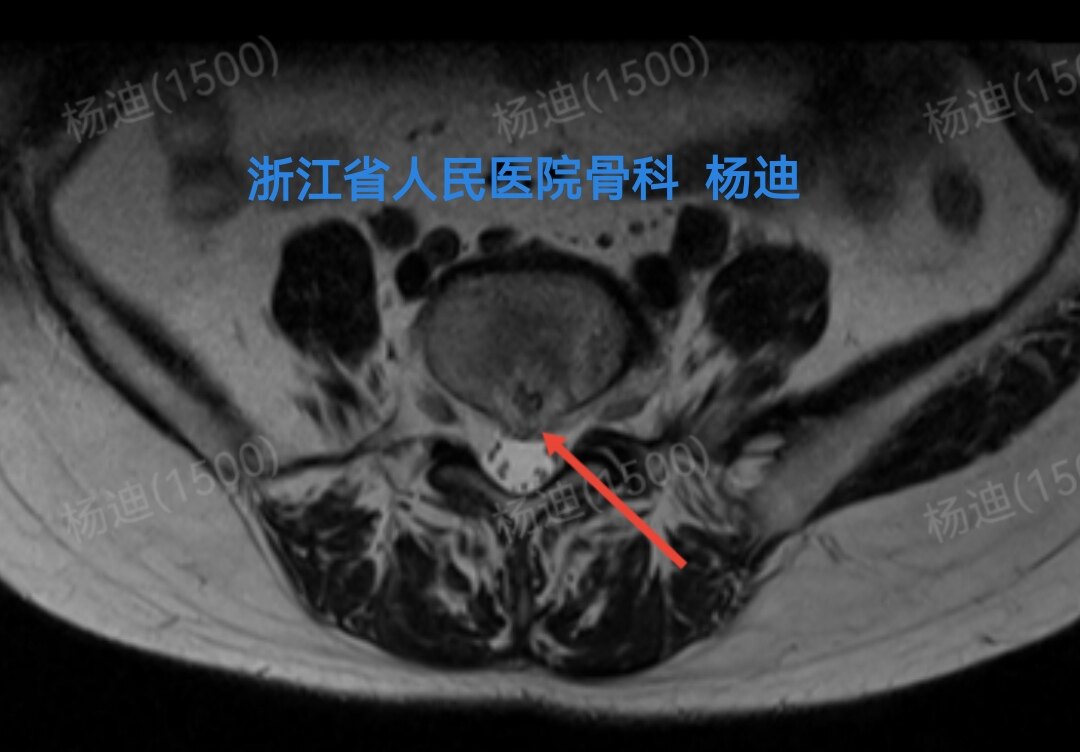

图为磁共振横断面检查结果,提示腰4/5椎间盘突出(红色箭头)。